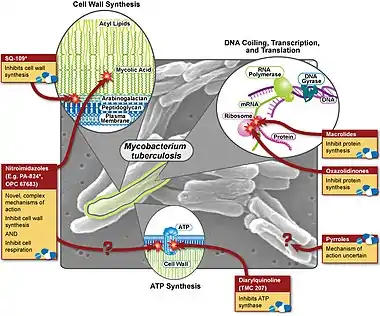

| Various pharmaceutical tuberculosis treatments and their actions | |